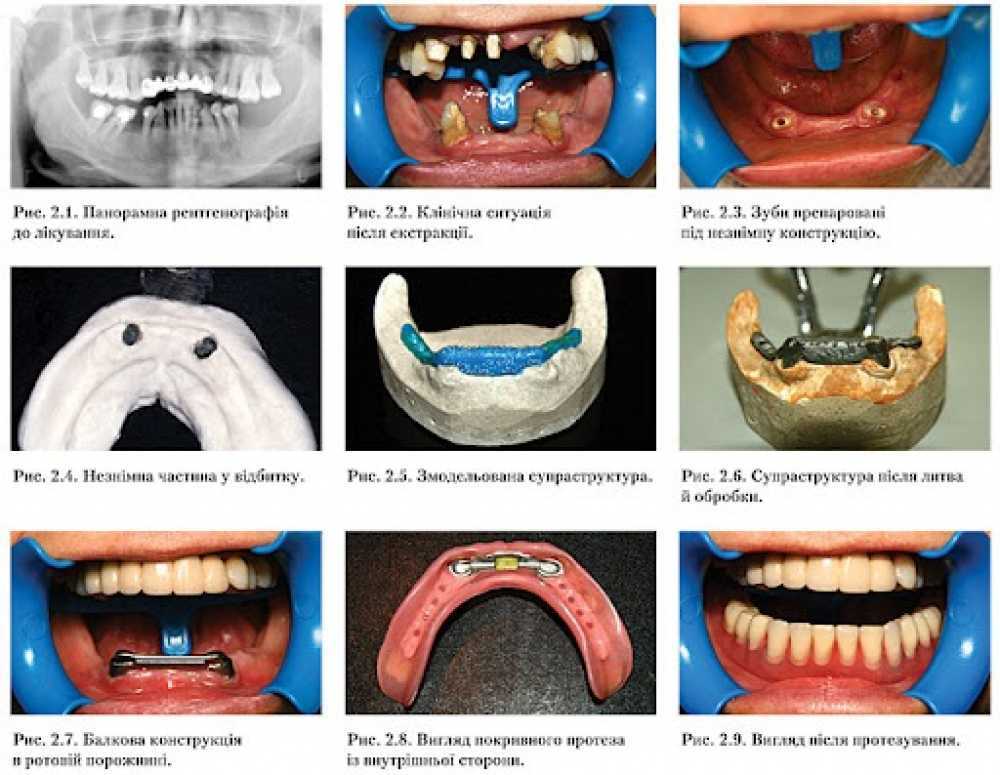

Балкові конструкції у протезуванні: теорія та цифрові рішення

Модуль 1. База. Підготовчі етапи - 2 год

Модуль 4. Вторинна структура на балках - 2 год